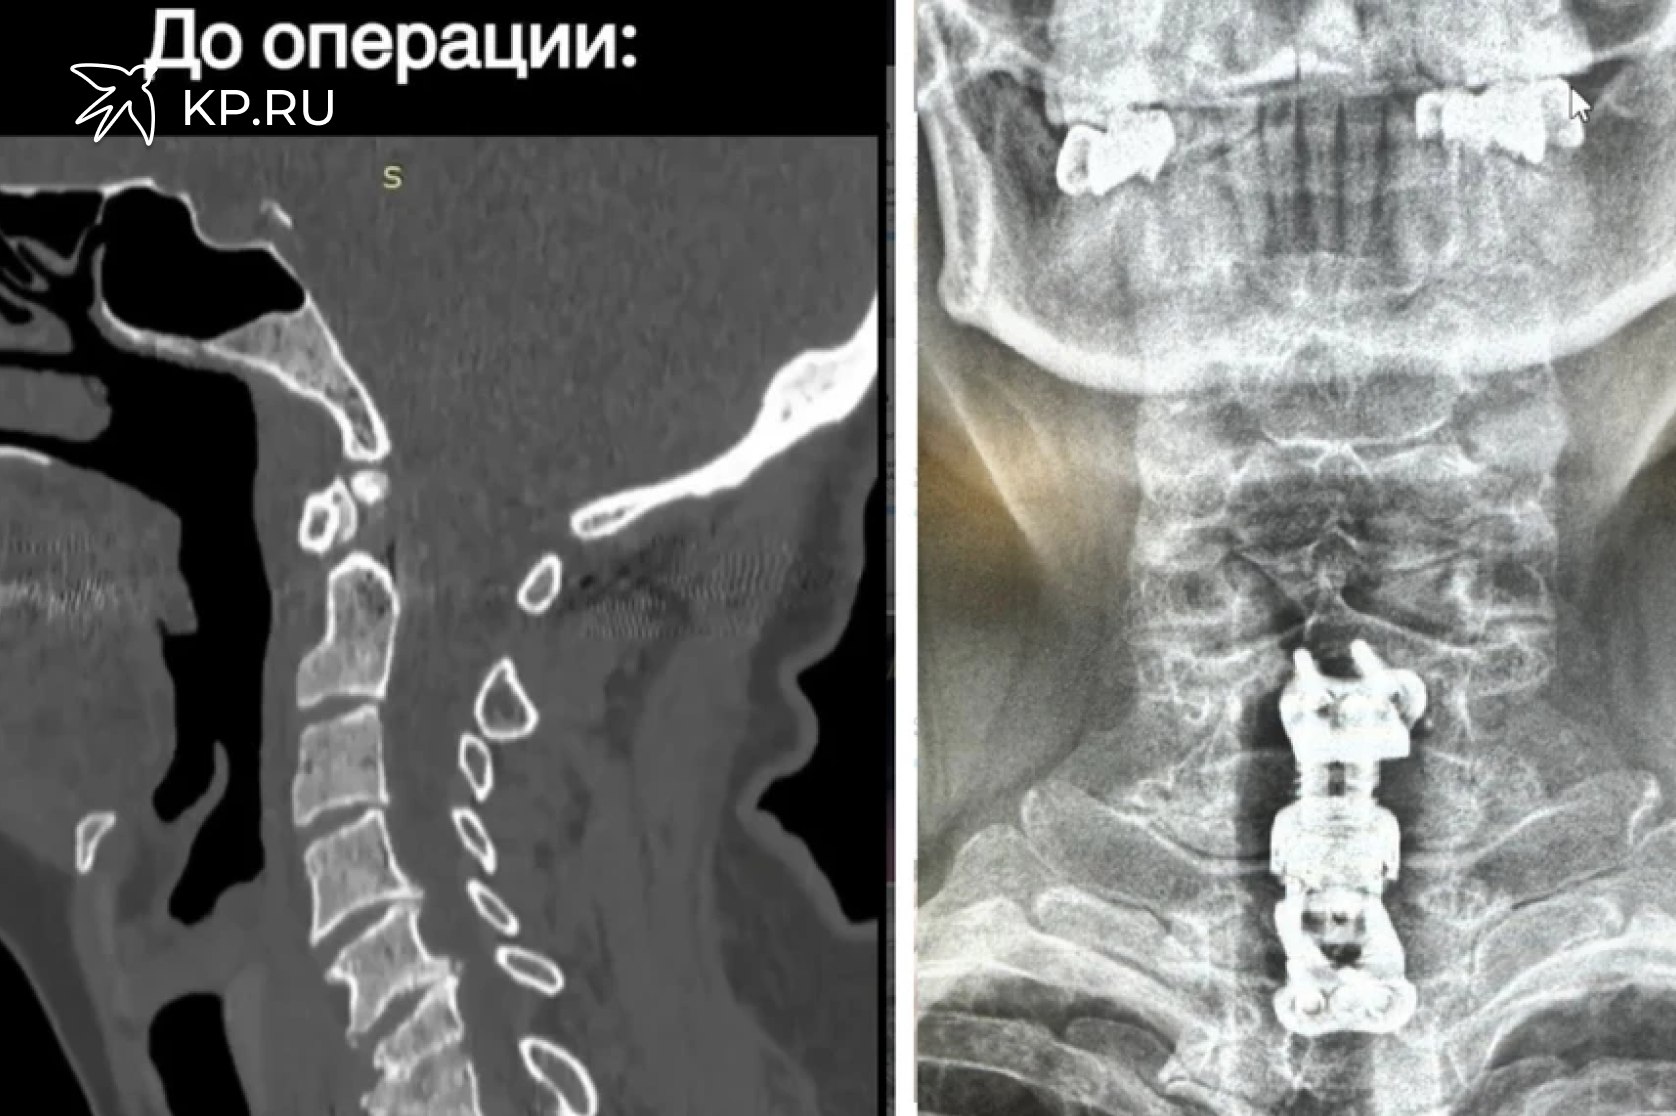

Жительнице Воронежа вживили имплант вместо двух удаленных шейных позвонков Воронежские врачи впервые поставили имплант вместо удаленных шейных позвонков 59 летняя пациентка еще в июле обратилась в БСМП 1 женщину беспокоили боли в шее и повышенная температура У нее выявили воспалительный процесс в межпозвонковом диске и двух позвонках Пациентке провели консервативное лечение купировав болевой синдром и нормализовав температуру Через две недели ее выписали Но спустя два месяца женщина снова обратилась с жалобами на боли в шее а также на онемение и неприятные ощущения в руках При дообследовании врачи выявили патологический перелом тел шестого и седьмого позвонков шейного отдела вследствие спондилодисцита Пациентке провели операцию удалив пораженные позвонки и устранив сдавливание спинного мозга После чего врачи установили телоскопичекий телозамещающий имплант который обеспечил стабильность в данных позвоночно двигательных сегментах После операции у пациентки прошли онемение и боль в руках женщину уже выписали